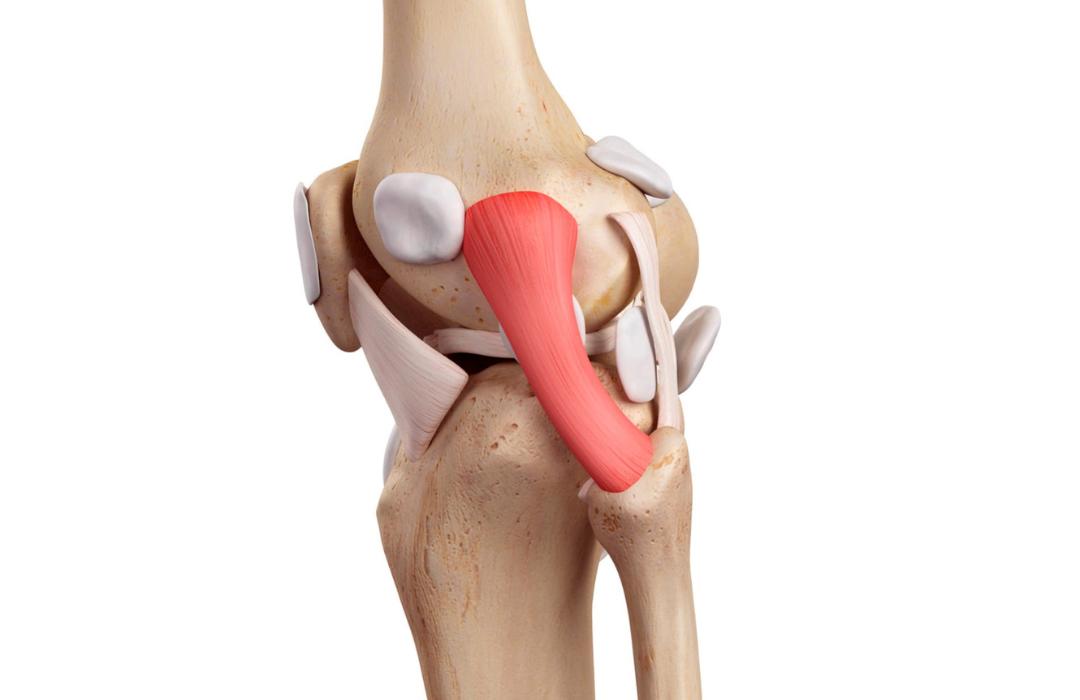

O joelho possui diversos ligamentos responsáveis por garantir estabilidade durante movimentos como caminhar, correr e mudar de direção.

Além dos cruzados, lesões nos ligamentos colaterais e estruturas estabilizadoras laterais podem comprometer gravemente a função do joelho.

Podem ser reconstruídos o LCA, LCP, LCM, LCL e estruturas do canto póstero-lateral. Muitos pacientes apresentam lesões combinadas que exigem reconstrução simultânea.